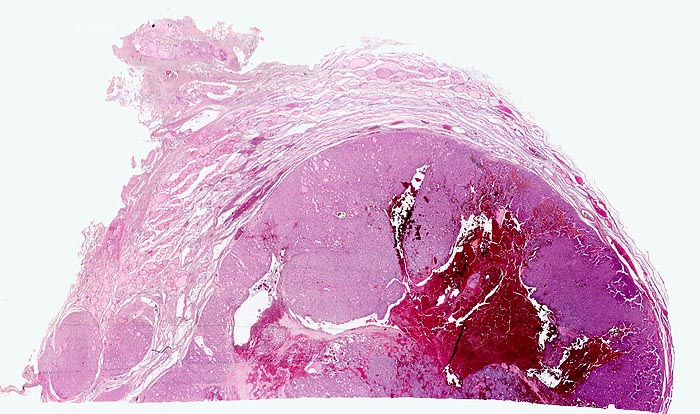

autonomes Adenom

benigner Tumor

Schilddrüse

Scharf begrenzter basophiler Knoten mit angedeuteter Kapsel und zentraler frischer Einblutung. Der Knoten komprimiert das angrenzende Schilddrüsenparenchym. Innerhalb des Knotens sind gar keine oder nur sehr kleine Follikellumina erkennbar. Zwei kleine Knoten mit ähnlicher Morphologie liegen unmittelbar neben dem grossen Knoten.